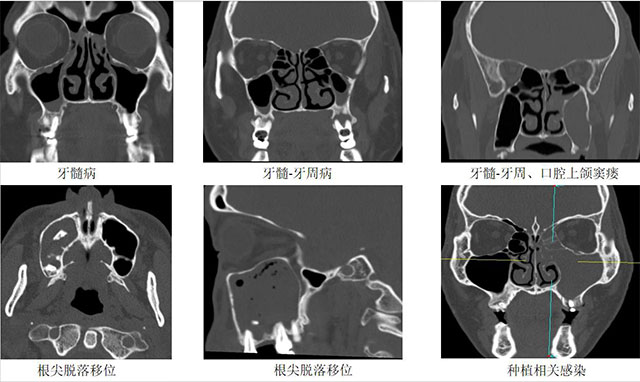

牙源性鼻窦炎是因牙齿感染扩散至上颌窦引发的炎症,属于上颌窦炎的特殊类型。由于上颌窦底部与上颌牙的牙根距离较近,中间仅隔一层薄骨板,当牙齿发生病变时,细菌或炎性物质可通过骨质破坏处侵入上颌窦,从而引发鼻窦炎症。

牙源性鼻窦炎的直接原因是牙齿或牙周感染蔓延至邻近的上颌窦。常见诱因包括:

1.根尖周炎:上颌磨牙或前磨牙的牙根距离上颌窦底仅数毫米,根尖感染可穿透骨壁侵入窦腔。

2.拔牙并发症:拔除上颌后牙时,若牙根进入上颌窦或造成窦底穿孔,可能引发感染。

3.牙周病或种植体感染:长期牙周炎或种植体周围炎可能向鼻窦扩散。